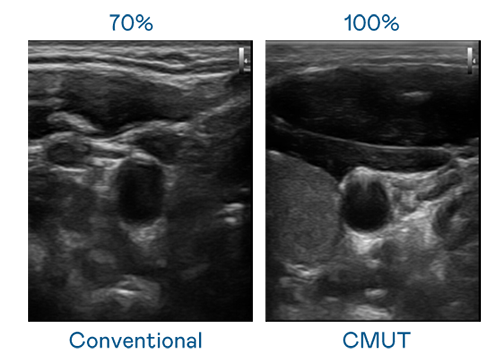

CMUT 技术是一种用电容式微机电元件来产生超音波讯号的技术。与传统 PZT 压电式技术相比,CMUT 频宽增加 30%,更宽频的超音波讯号让影像解析度大幅提升,是实现高影像品质医疗超音波扫描、促进精准医疗发展的关键技术。

超音波影像的解析度高低,首先取决于探头能发出的讯号频宽。j9九游会(中国)官方网站 CMUT 可提供高清晰的超音波讯号,提供高频宽、高灵敏度、影像纹理细节更高的超音波影像,协助医护人员缩短影像判读时间及利用精准的医疗影像进行诊断。